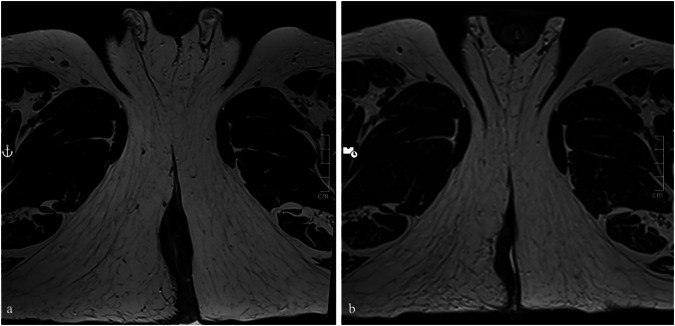

Methods: We manually annotated pretreatment T2-weighted turbo spin-echo images of 26 consecutive patients with stage III SCC of the anal canal treated with CRT at our institution from 2012 to 2022. Each patient was classified as complete response (CR, 17 patients), or non-complete response (non-CR, 9 patients) based on the absence or presence of residual disease at imaging and endoscopy after treatment. A total of 132 three-dimensional radiomic features were extracted for each patient and fed to a dedicated machine-learning classifier.